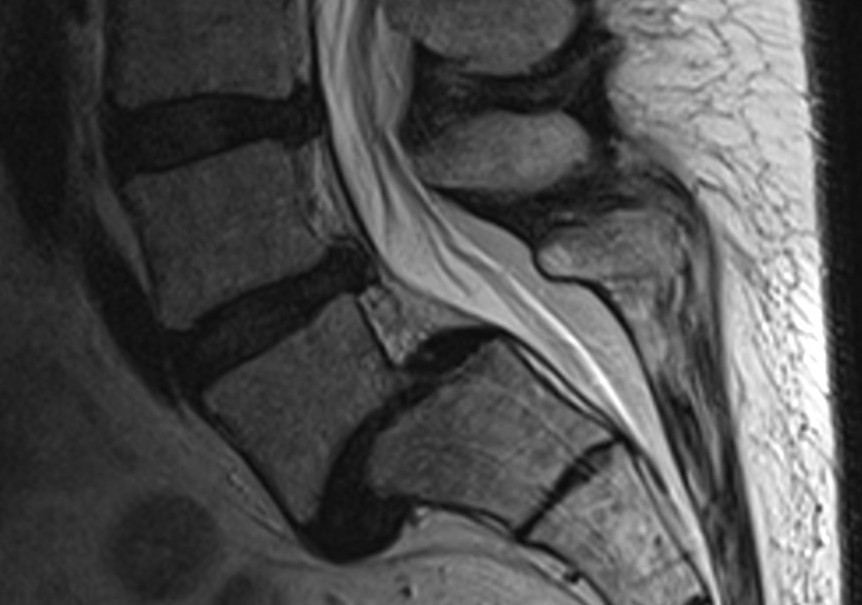

Spondylolisthesis

Occurs when one vertebra becomes anteriorly displaced over the one below it. Most often involves 4th or 5th lumbar vertebrae. Due to compression of the spinal nerves, this condition can cause pain in the low back/lower extremity.